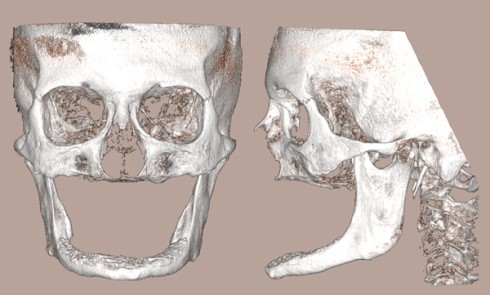

Article réservé à nos abonnés Atrophie maxillaire extrême

La chirurgie pré-implantaire est bien décrite [1] et peut consister en des greffes d’apposition et/ou des comblements sinusiens avec des...